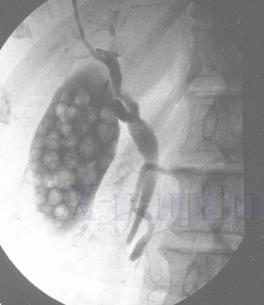

мал. 9 АЛегені

Мал. 2 А. Рентгенографія легень

Часто застосовуються у клінічній практиці і базуються на просвічуванні окремих частин тіла рентгенівськими променями за рентгенівським екраном (рентгеноскопія). На екрані можна побачити тіні різної прозорості: на фоні прозорих легень можна виявляти ділянки ущільнення легеневої тканини, визначати розміри і конфігурацію серця.

Для фіксації виявлених змін проводять рентгенографію легень (мал. 2 А) – знімають зображення на плівку, що засвічується рентгенівськими променями. На рентгенівській плівці отримують негативне зображення (світлі місця на рентгенівському екрані і навпаки темні – на плівці).

мал.10А. КТ

мал.10Б. КТ легень

А

Б

Мал. 5. Компютерна томографія легень

Комп'ютерна томографія є найбільш інформативним методом рентгенодіагностики. Сфера її застосування дуже широка.

Вона дає змогу чітко диференціювати структури тканин і середовищ за щільністю (кров, рідина, пухлина, межі тканин), завдяки чому можна визначити локалізацію і поширення патологічних процесів в органах і тканинах. Інформація надходить на комп’ютер, що перетворює її на зображення у вигляді поперечного зрізу досліджуваного органу. Зображення можна отримати на екрані телемонітора, плівці та полероїдному слайді (рентгенотелебачення).